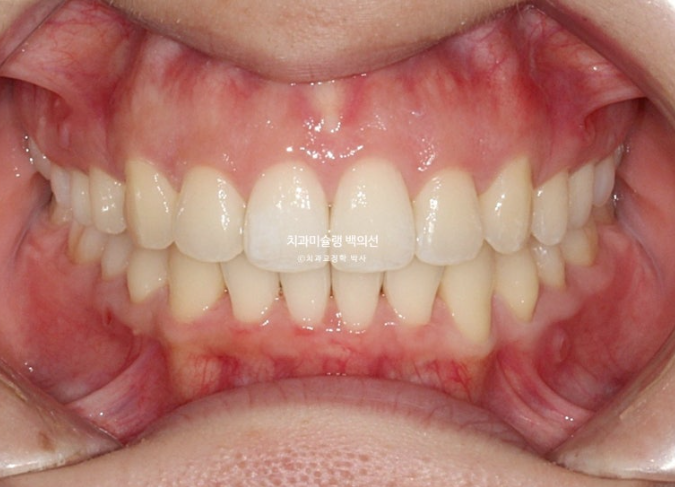

교합은 이미 1급 교합관계로 완성 상태입니다.

배열도 완벽합니다.

블랙트라이앵글 사이즈는 많이 줄였고 중심선은 잘 맞습니다.

어금니 교합은 물샐틈 없는 1급관계입니다.